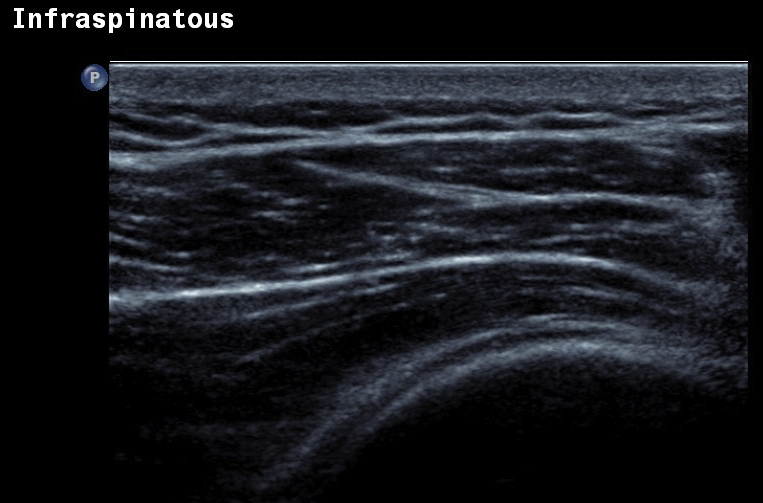

Ultrasound

Normal

- systematic review of US rotator cuff tears

- US more accurate for supraspinatus and biceps than subscapularis

- US more accurate for full thickness tears than partial thickness tears